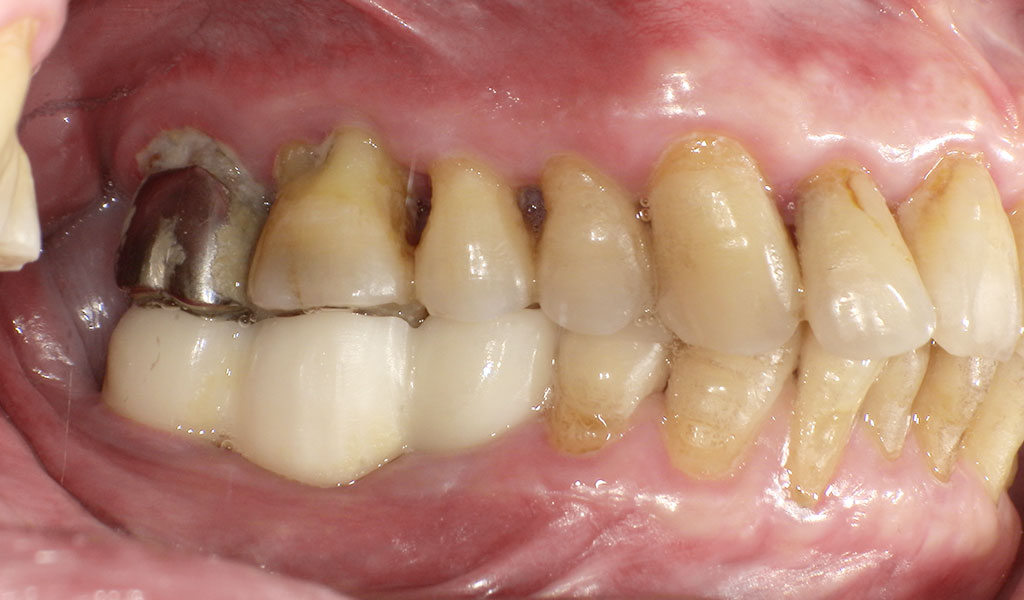

Before(左下6,7番、右下5,6,7番)

Before(左上6番、下6,7番)

Before(右下5,6,7番)